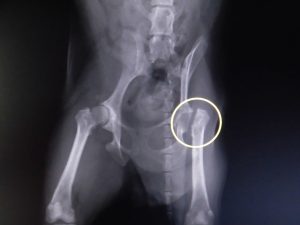

犬の大腿骨頭壊死症(レッグ・ペルテス)